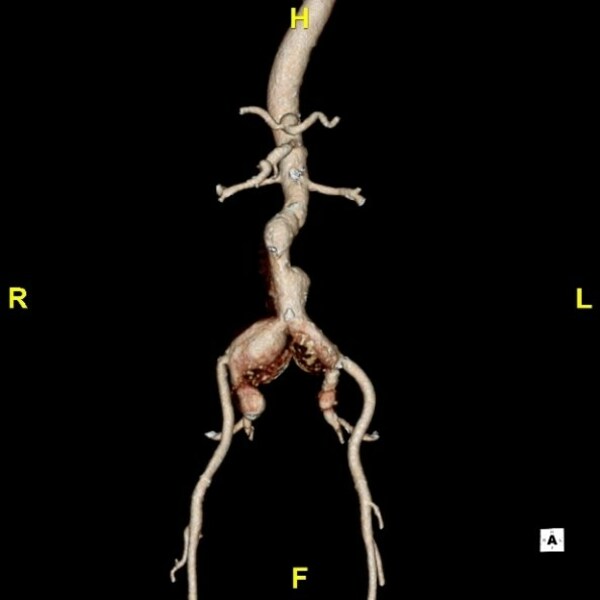

術(shù)前CTA

患者男性,近70歲,體檢時發(fā)現(xiàn)雙側(cè)髂動脈夾層動脈瘤相較之前進(jìn)展,遂收入德達(dá)醫(yī)院治療。3年前因急性A 型主動脈夾層進(jìn)行手術(shù)治療,術(shù)后恢復(fù)良好,且定期復(fù)查;近期就診,進(jìn)行主動脈CTA 檢查提示:腹主動脈瘤累雙側(cè)髂總動脈,較之前有進(jìn)展,需要進(jìn)一步治療。